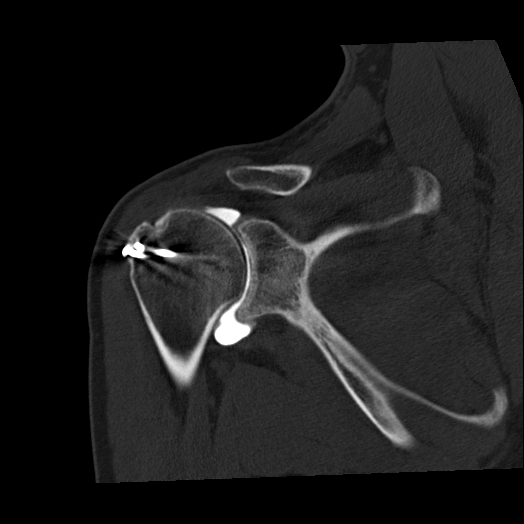

Konsultacja radiologiczna narządu ruchu to bezpośrednia rozmowa z radiologiem, która wykracza daleko poza standardowy opis badania. To spotkanie, podczas którego lekarz radiolog szczegółowo analizuje obrazy z badań diagnostycznych (rezonans, tomografia, RTG), wyjaśnia znaczenie widocznych zmian i odpowiada na pytania Pacjenta. W przeciwieństwie do tradycyjnej ścieżki, gdzie opis trafia bezpośrednio do lekarza prowadzącego, konsultacja daje Pacjentowi możliwość bezpośredniego kontaktu z osobą, która analizowała jego badanie. To usługa, która pomaga zrozumieć wyniki, rozwiać wątpliwości i uzyskać pełen obraz swojego stanu zdrowia.

Zrozumienie medycznego żargonu – opisy radiologiczne pełne są hermetycznej terminologii, która brzmi groźnie, nawet gdy nie musi być powodem do niepokoju. Radiolog pokazuje na konkretnych obrazach, gdzie znajdują się zmiany i co one rzeczywiście oznaczają.

Obiektywna ocena zmian – radiolog potrafi odróżnić zmiany istotne klinicznie od naturalnych procesów starzenia się organizmu, które nie wymagają leczenia. Wiele zmian widocznych w badaniach to po prostu skutki upływu czasu, niekoniecznie powodujące objawy.

• Gdy masz kilka badań z różnych okresów – chcesz wiedzieć, czy zmiany się pogorszyły, czy leczenie przynosi efekty, czy obserwujesz progresję choroby.